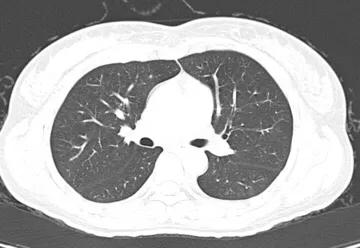

正常胸部CT图像

冠状位重建CT胸部图像